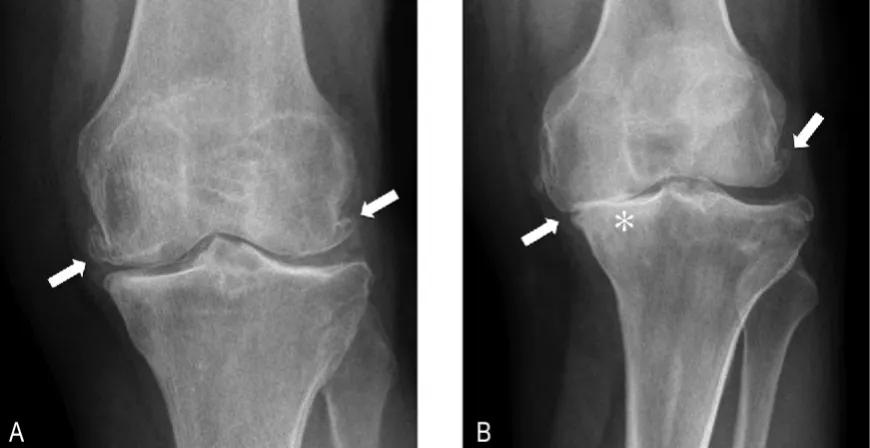

骨关节炎,也叫 退变性关节炎 或 老年性关节炎 ,其主要的病理基础就是 关节内软骨的磨损 ,随着年龄的增长、长期的使用以及外伤等因素,关节软骨表面不再光滑,磨损日渐加重,患者就会出现关节的疼痛、酸胀以及功能受限,严重的会导致残疾,它是老年人致残的主要原因之一。

但有一点要注意,那就是 骨关节炎患者的病情不能太重,适合早期和中期患者服用 ,如果经过检查患者的关节软骨磨损极其严重,关节间隙出现了明显的狭窄,关节周边已经有大量的骨赘形成,到了骨关节炎晚期的程度,就没有必要尝试了, 雄狮已经消失了,再补充养分也于事无补了 ,就是这个道理。